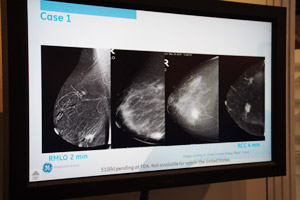

デジタルマンモグラフィは,同社最上位機種の「Senograph Essential」が展示された。RSNA 2009では,従来よりも一回り大きな24cm×24cmのFPDを搭載し,将来のAdvanced Applicationのプラットフォームとなる製品として発表されたが,実際に今回の展示では,Advanced Applicationとして,新しい造影マンモグラフィ技術である“Contrast Enhanced Spectral Mammography(CESM)”が紹介された。CESMは,ヨード造影剤のX線吸収特性を利用し,造影剤投与後に通常のマンモグラフィ撮影と同じ方法でDual Energyでの撮影を行い,画像処理によってバックグラウンドの乳腺信号を抑制しつつ造影剤信号を強調することで病変を抽出する技術。従来の2Dの画像情報に加えて,血流動態情報は得られないが,特に,乳腺密度の高い患者の多い日本やアジアでの有用性が期待されている。すでに欧米では,MRIとの比較研究が進められており,存在診断や鑑別診断,広がり診断などにおいて,多くの有用性が確認されているという。

Senograph EssentialによるCESMの画像